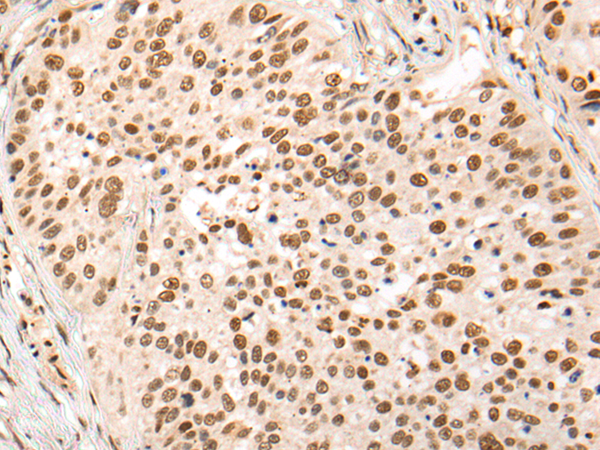

分类: 科研抗体货号: P04568别名: ANTP; HOX1; HOX1A; HOX1.1应用: IHC反应种属: Human, Mouse